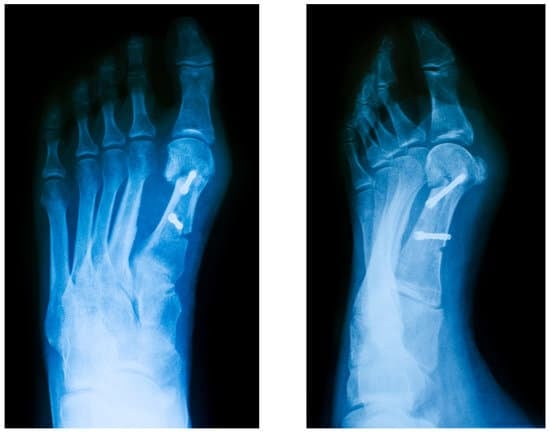

절골술

절골술은 발의 변형된 뼈를 절단하여 올바른 위치로 재정렬하는 수술입니다. 이 수술은 변형이 심한 경우에 주로 시행됩니다.

방법:

변형된 뼈를 절단합니다.

뼈의 위치를 재정렬합니다.

금속 핀이나 나사를 사용하여 뼈를 고정합니다.